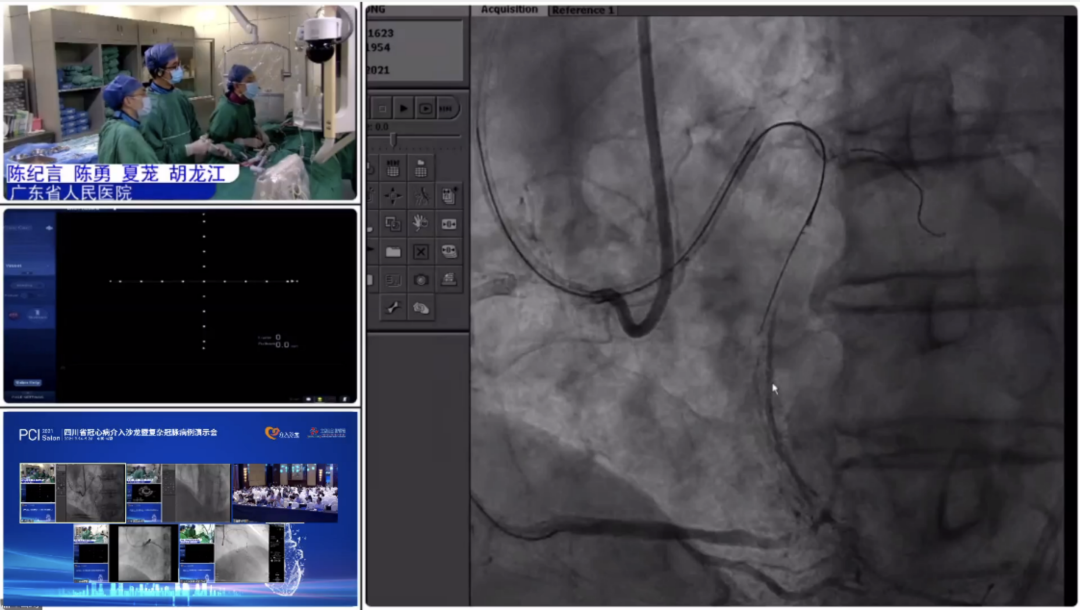

9月25日,大会隆重开幕,大会执行主席、四川大学华西医院贺勇教授主持,大会创始人及名誉主席、四川大学华西医院心内科黄德嘉教授,北京力生心血管健康基金会管廷瑞理事长,大会主席、四川大学华西医院陈茂教授,大会创始人及名誉主席东莞康华医院贾国良教授等多位专家领导分别以线上、线下参会形式共同出席开幕式,并为大会开幕致辞。随后,来自全国多地的冠脉领域资深术者通力配合,带来了11场极具难度和技巧的复杂冠脉病例手术演示及微课讲座。同期进行的护理及技术人员论坛、冠脉腔内影像与生理学论坛、冠心病诊疗论坛、降脂治疗论坛&心衰药物进展论坛、血栓抽吸、药物球囊、愈合型支架等专题学术内容应接不暇、精彩纷呈。